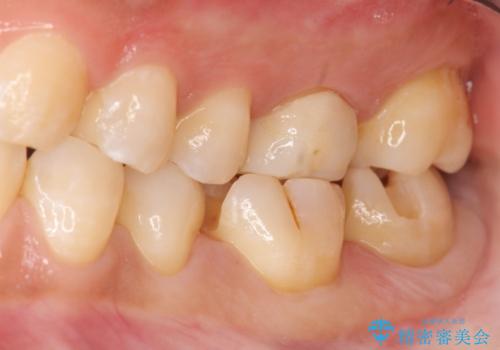

左下の奥歯2本にプラスチックの詰め物がされており、一見虫歯には見えない状態でした。

古い詰め物を取り、虫歯を除去して、合わせた形でセラミックインレーで治療しました。

- 14万円(内訳 左下67:セラミックインレー 7万円 x 2本)費用は治療当時の料金となります